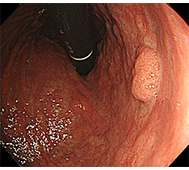

食道がん

日本では、60歳代の男性に好発し、男女比は、3:1程度です。 そのほとんどが扁平上皮癌で、発生部位は胸部中部食道に多くみられます。 原因として飲酒と喫煙があげられます。

- 内視鏡治療 :病変がリンパ節転移の無い早期食道がんに対し、内視鏡治療が行われます。